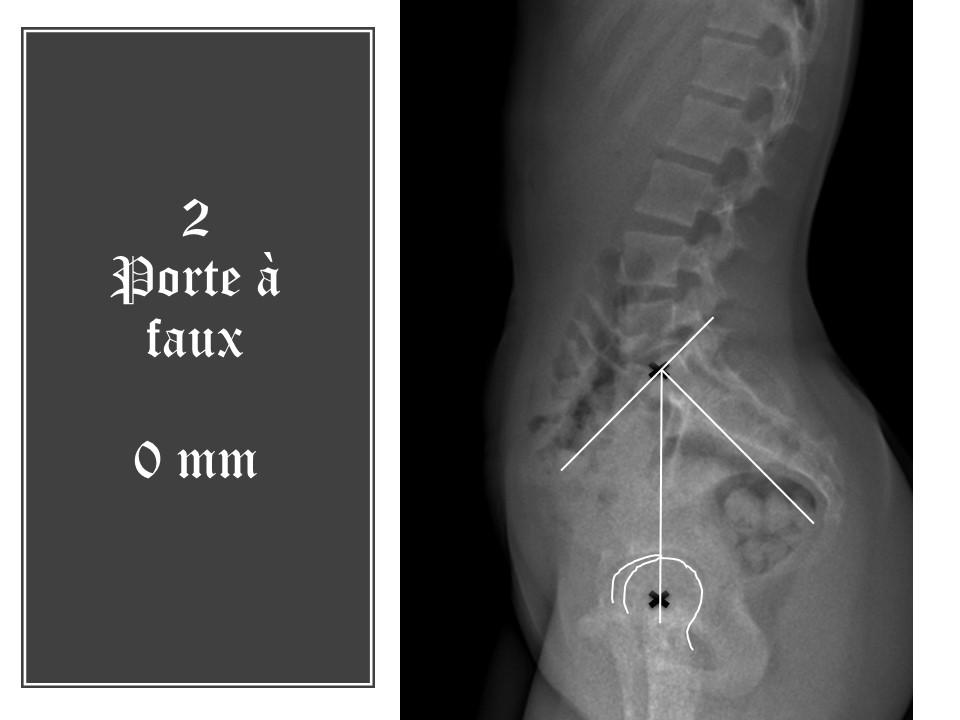

Le porte-à-faux correspond à la distance entre la ligne verticale abaissée du centre de la plaque sacrée au centre des têtes fémorales. Ici, le porte-à-faux est nul, ce qui correspond à une antéversion du bassin.

L'incidence pelvienne est égale à la somme de l'inclinaison pelvienne et de la pente sacrée (PI=PT+SS). La bascule du bassin est donc ici de 3°, ce qui confirme l'antéversion du bassin. Compte tenu de l'incidence pelvienne, la bascule pelvienne devrait être de 10°. Il y a donc une anomalie de la statique dans le plan sagittal.